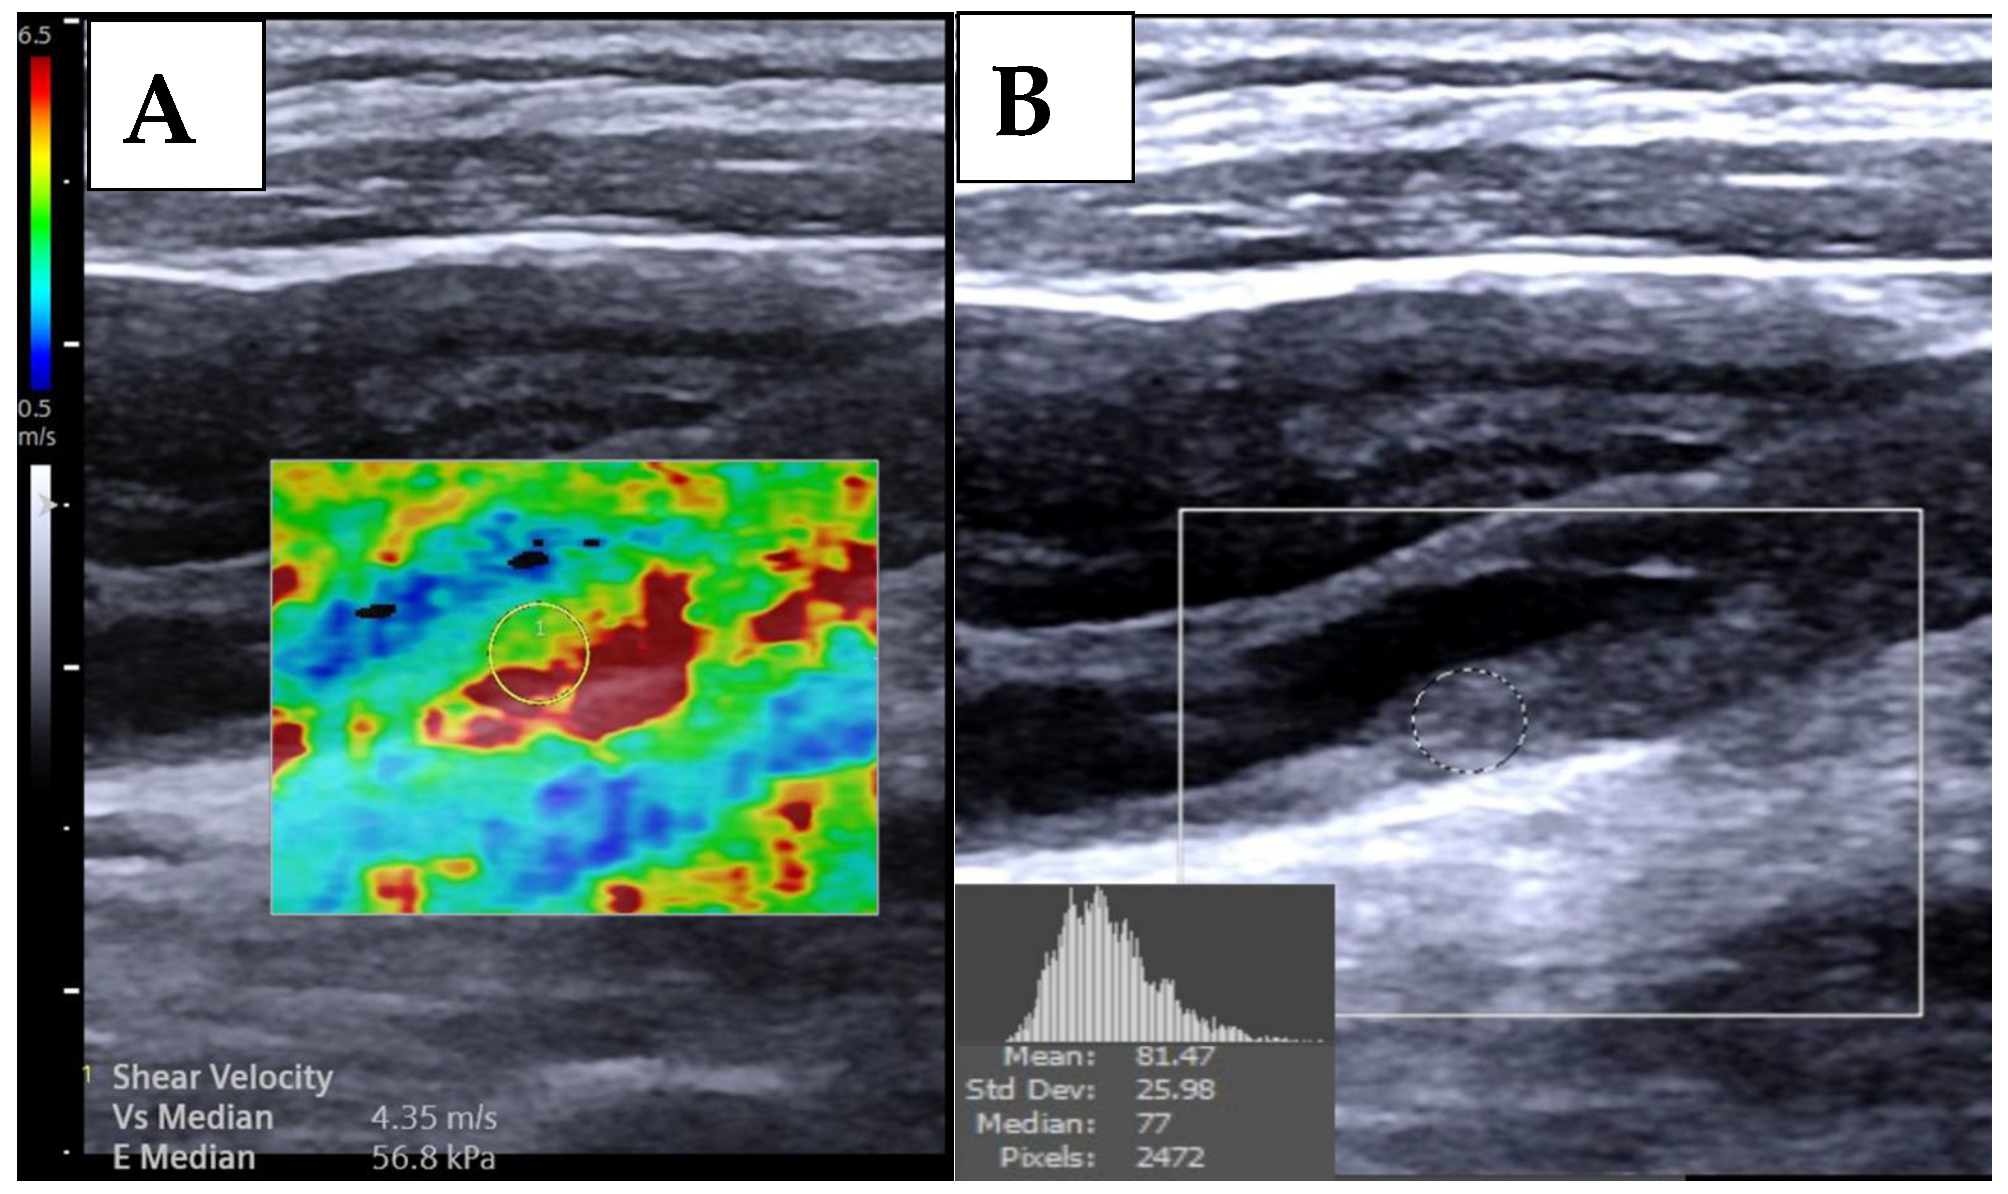

| 2D-SWE, median [IQR, m/s] | 3.85 [2.54] | 3.64 [1.02] | 4.91 [1.69] | <0.001 |

| 2D-SWE, median [IQR, kPa] | 44.53 [59.48] | 20.96 [17.30] | 72.54 [48.39] | <0.001 |